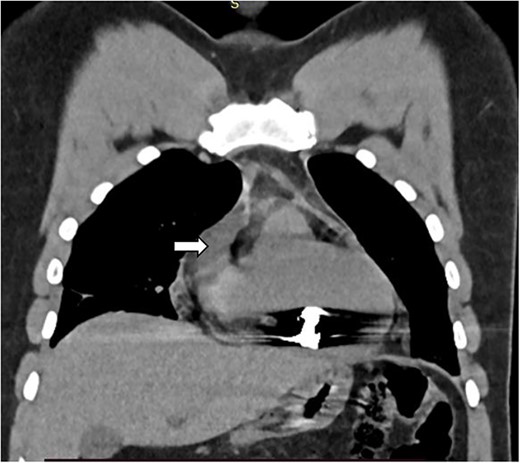

The complete blood count showed white cell count of 4300 cells, hemoglobin of 18.7 g/dl, and platelet of 285 000. Serum electrolyte, albumin and liver function tests were within normal range and creatinine was 1.19 mg/dl. Chest X ray showed bullet left of the sternum within the inferior aspect of the cardiac silhouette. Contrast CT scan detected minimal bilateral pleural collection with right basal segment atelectasis with 2.3 × 1.1 cm metallic density foreign body in the mediastinum located over the inferior border of ventricular wall (Figs 1–3). Troponin was 432.4 ng/ml. Electrocardiography showed V2 lead ST segment elevation. All the other leads were normal. The patient had three echocardiographs done, and only one showed the presence of foreign body within the myocardium of the left ventricle. Otherwise, no wall motion abnormality, or any sign of heart failure was detected.

Sagittal image depicting foreign body within the myocardium (white arrow).